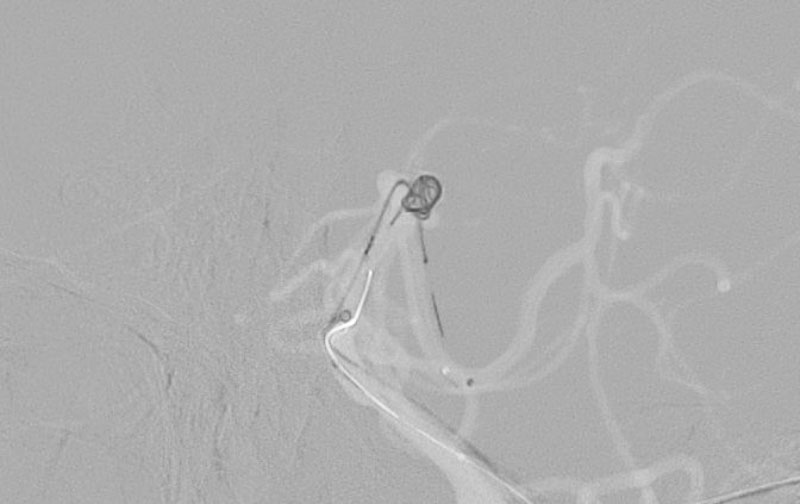

No.1588 手術前

No.1588 手術中

No.1588 手術後

'25年10月

くも膜下出血

前交通動脈瘤破裂

60代

救急外来